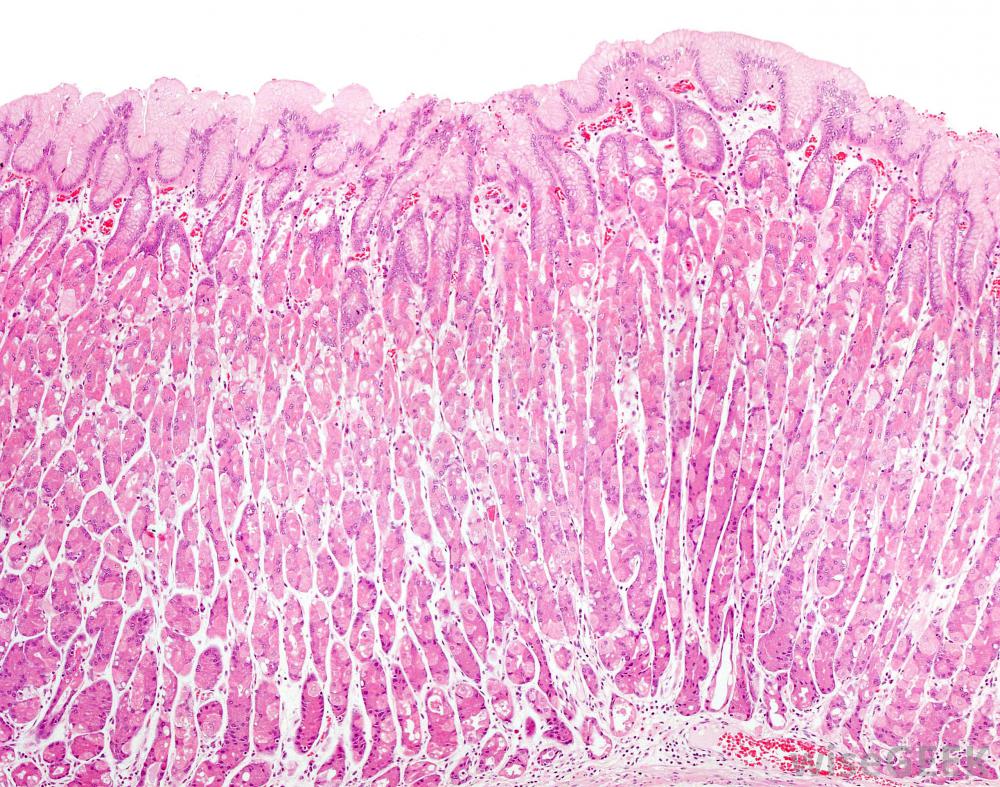

一項研究發現,白茶可能刺激或炎癥胃壁細胞。

然而,一項關于白茶的研究應該讓那些有胃病的人警覺起來。白茶和綠茶實際上可能會使胃壁發炎,這稱為胃炎。那些以前患過胃炎的人最容易受到這種副作用的影響。

白茶和綠茶可能會使胃壁發炎。